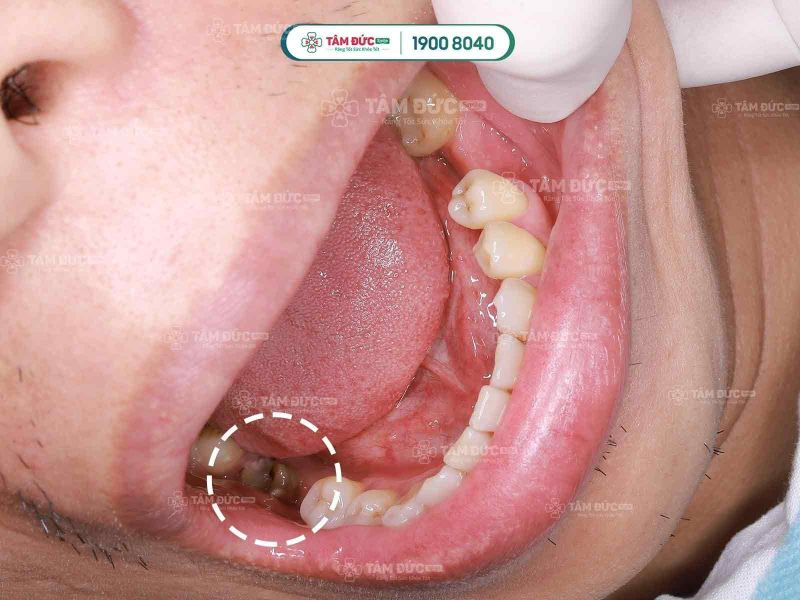

1. Chữa tủy răng răng sâu?

Tủy răng là các mô nhỏ dạng sợi chứa nhiều mạch máu và dây thần kinh nằm ở chính giữa răng, đóng vai trò cung cấp chất dinh dưỡng cũng như nuôi sống răng. Nếu trong trường hợp tuỷ răng này bị viêm nhiễm hay tổn thương vì bất cứ nguyên nhân nào thì chữa tuỷ răng là điều vô cùng cần thiết để giữ lại được răng thật, tránh trình trạng phải nhổ bỏ răng.

Nội nha chữa tủy là kỹ thuật nha khoa hiện đại giúp loại bỏ sạch những phần mô tủy răng đã bị chết, hoại tử hoặc viêm nhiễm. Sau khi lấy hết các dịch tủy, khoảng trống còn lại được làm sạch, tạo dáng và trám bít lại, tránh hiện tượng bệnh lây lan nhanh, gây hại đến sức khỏe răng miệng.